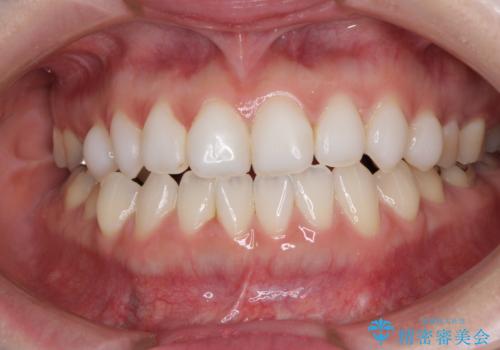

前歯のデコボコをすっきりと インビザライン矯正

担当医 藤巻太一朗